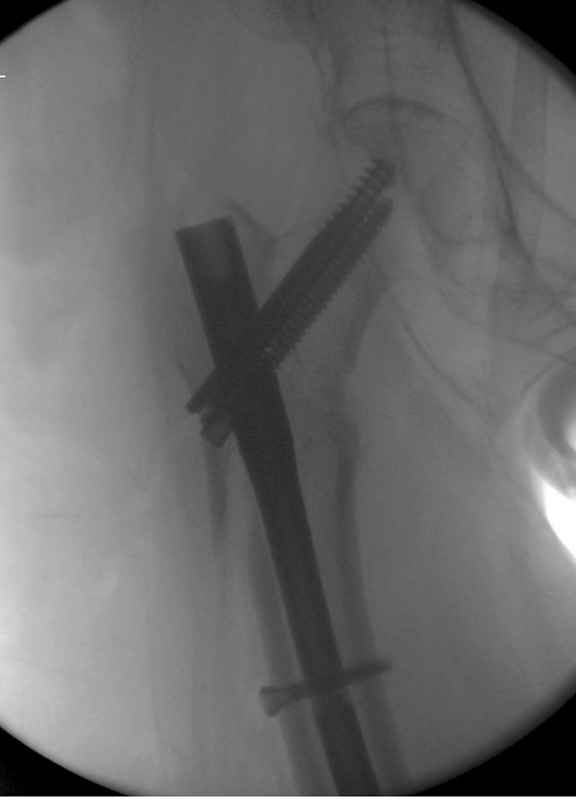

Из фиксаторов, мы бы применили цефаломедуллярные, потому что они "по закону моментов" из-за короткого рычага от центра головки к диафизу и по принципу "головка диафиз" механически лучше выдерживают нагрузки, чем пластины.

Но современные пластины с угловой стабильностью не отстают от медуллярных конструкций. Межфрагментарные шурупы и имплант как нейтрализирующее создаст адекватную фиксацию.

Здесь пара случаев фиксации похожих переломов:

первый высокоэнергетическая травма 36 лет

судя по картинкам с ЭОПа явно использовались приемы непрямой репозиции под его контролем, а так же интраоперационный ЭОП-контроль положения винтов, без такого контроля операция может ухудшить ситуацию (опять же учтите сроки) т.к. результат буде зависеть в большей степени от искусства хирурга, а не от технологии